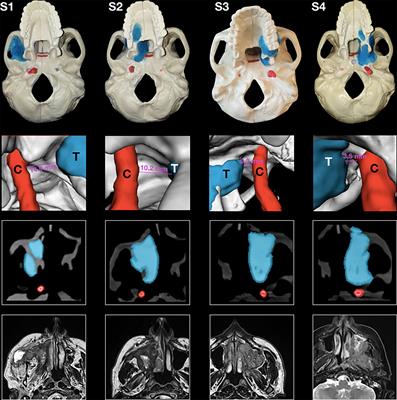

in Veterinary Dentistry and Oromaxillofacial Surgery